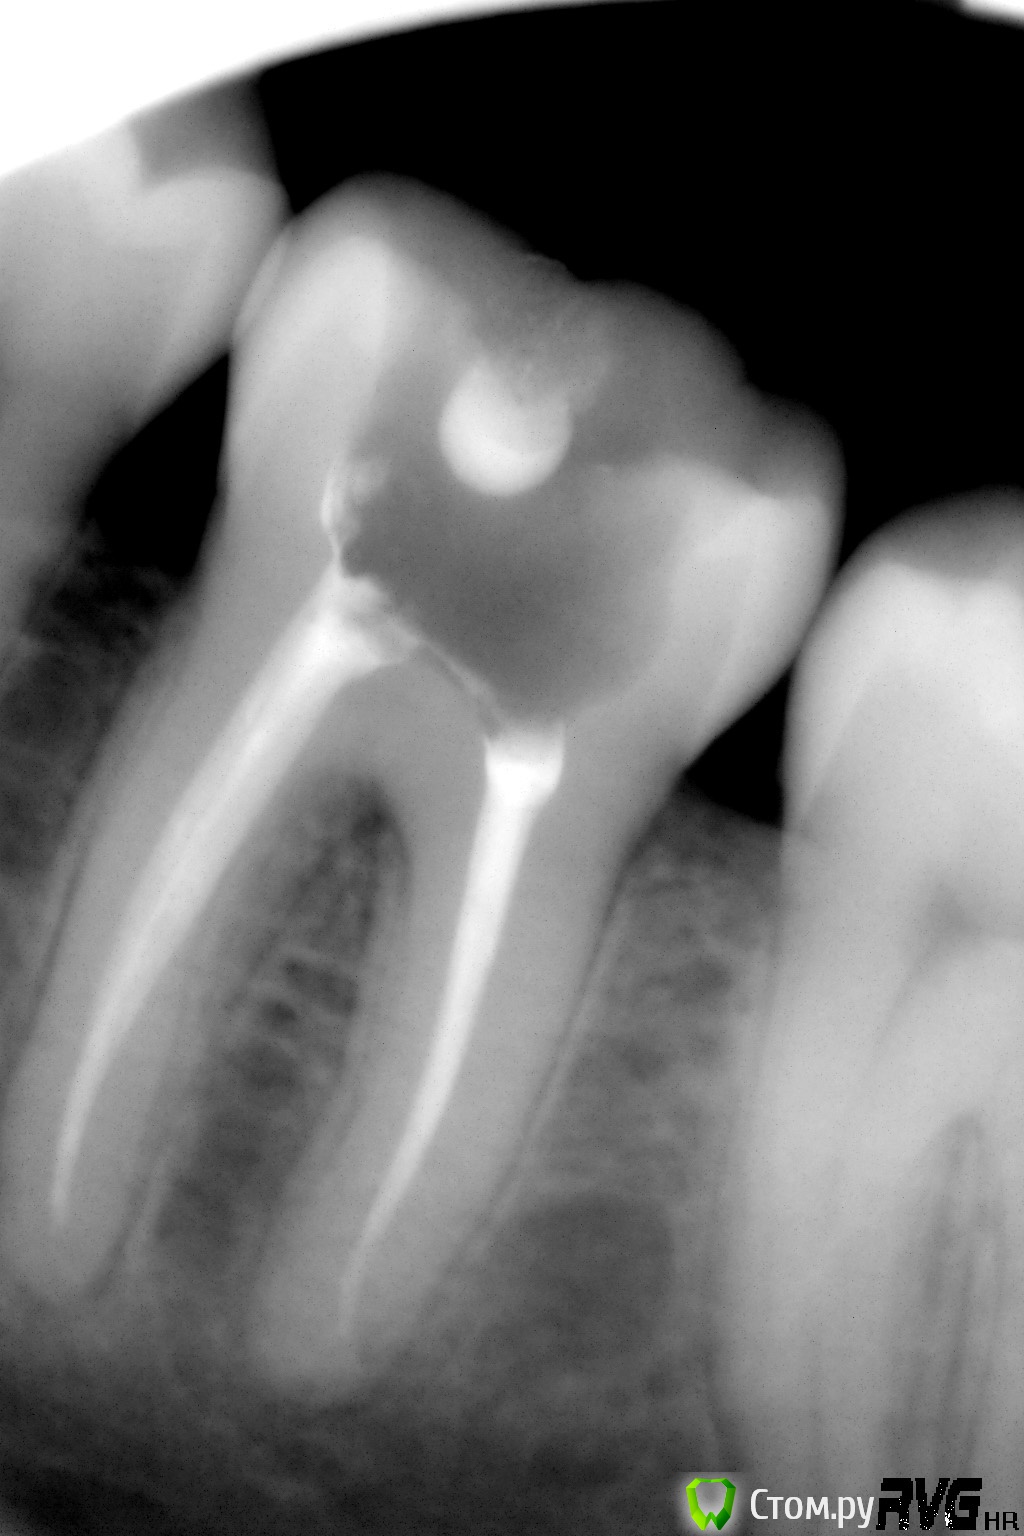

Afffinity Опубликовано 17 марта, 2014 Поделиться Опубликовано 17 марта, 2014 1. Обратился мужчина, 25 лет, с жалобами на боли от холодного и горячего в области 36 зуба. На жевательной поверхности как таковой кариозной полости не было. Осталась полость от выпавшей пломбы. Когда выпала не уточнял, но зуб беспокоил 3й день. Как говориться, пипец один не приходит, а рядом с собой везет маленькую тележку. Сделали панорамник:Помимо эндо 36 было еще и эндо 31. Благо пациент разумный был. конечный результат тутИнструментация М-ту до 30/05. Ирригация гипохлорит, вода, ЭДТА, гипохлорит, сушка. Пломбирование вертикалка(Аппарат от Сиброн эндо, скажу не очень убобный. Бифилл лучше). Востановление композитный билдап. Апикальная часть обработана до 40/04 (дентин был мягкий, поэтому и расширять пришлось как следует). В ближайшее время будем вызванивать на реколл. Ссылка на комментарий

шахтер Опубликовано 17 марта, 2014 Поделиться Опубликовано 17 марта, 2014 1. Обратился мужчина, 25 лет, с жалобами на боли от холодного и горячего в области 36 зуба. На жевательной поверхности как таковой кариозной полости не было. Осталась полость от выпавшей пломбы. Когда выпала не уточнял, но зуб беспокоил 3й день. Как говориться, пипец один не приходит, а рядом с собой везет маленькую тележку. Сделали панорамник:Астафьев панорам..jpgПомимо эндо 36 было еще и эндо 31. Благо пациент разумный был. конечный результат тутR1.jpgИнструментация М-ту до 30/05. Ирригация гипохлорит, вода, ЭДТА, гипохлорит, сушка. Пломбирование вертикалка(Аппарат от Сиброн эндо, скажу не очень убобный. Бифилл лучше). Востановление композитный билдап. R3.jpgАпикальная часть обработана до 40/04 (дентин был мягкий, поэтому и расширять пришлось как следует). В ближайшее время будем вызванивать на реколл. А что 26,27,28,37? Снимок мало информативен . Нужна кт . Ссылка на комментарий

Afffinity Опубликовано 17 марта, 2014 Автор Поделиться Опубликовано 17 марта, 2014 Почему тогда дист стенка целая?Она "почти" целая была. На контактной поверхности в эмали едва заметное входное отверстие было. Но после вскрытия все было заполнено мягким дентином. Хорошо заметно было только при визуальном осмотре. Ссылка на комментарий